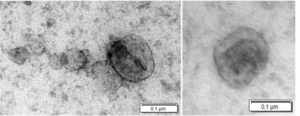

Τίτλος Ερευνητικού Έργου: «Καινοτόμος θεραπευτική προσέγγιση βασισμένη σε εξωσωμάτια προερχόμενα από μεσεγχυματικά βλαστικά / στρωματικά κύτταρα για την οξεία ηπατική ανεπάρκεια»

Επιστημονική Υπεύθυνη: Ρουμπελάκη Μαρία